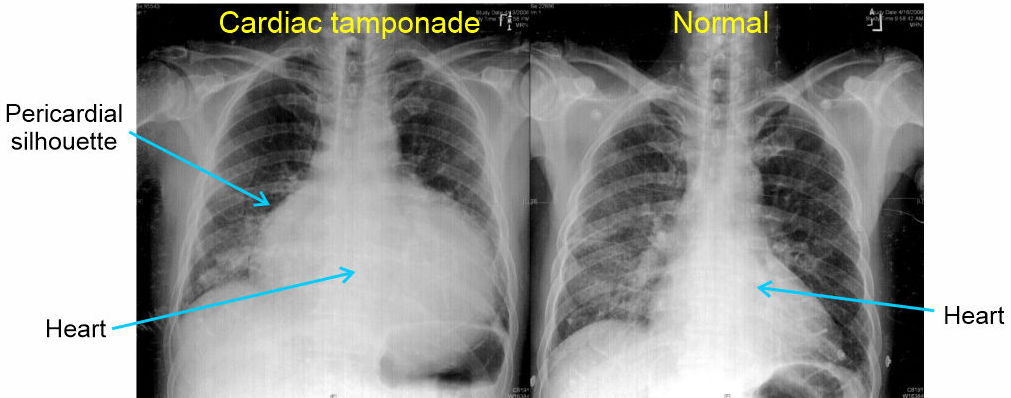

Diagnosis is usualy through a combination of clinical signs of Beck's Triad and ultrasound imaging. A chest x-ray is typically not a common choice of imaging modality for diagnosis, however a CTX is very useful to assess efficacy of treatment interventions. If an x-ray is performed, cardiac tamponade presents as an enlarged pericardial silhouette (outlne) formed into a globular or water bag shape due to the fluid in the sack.